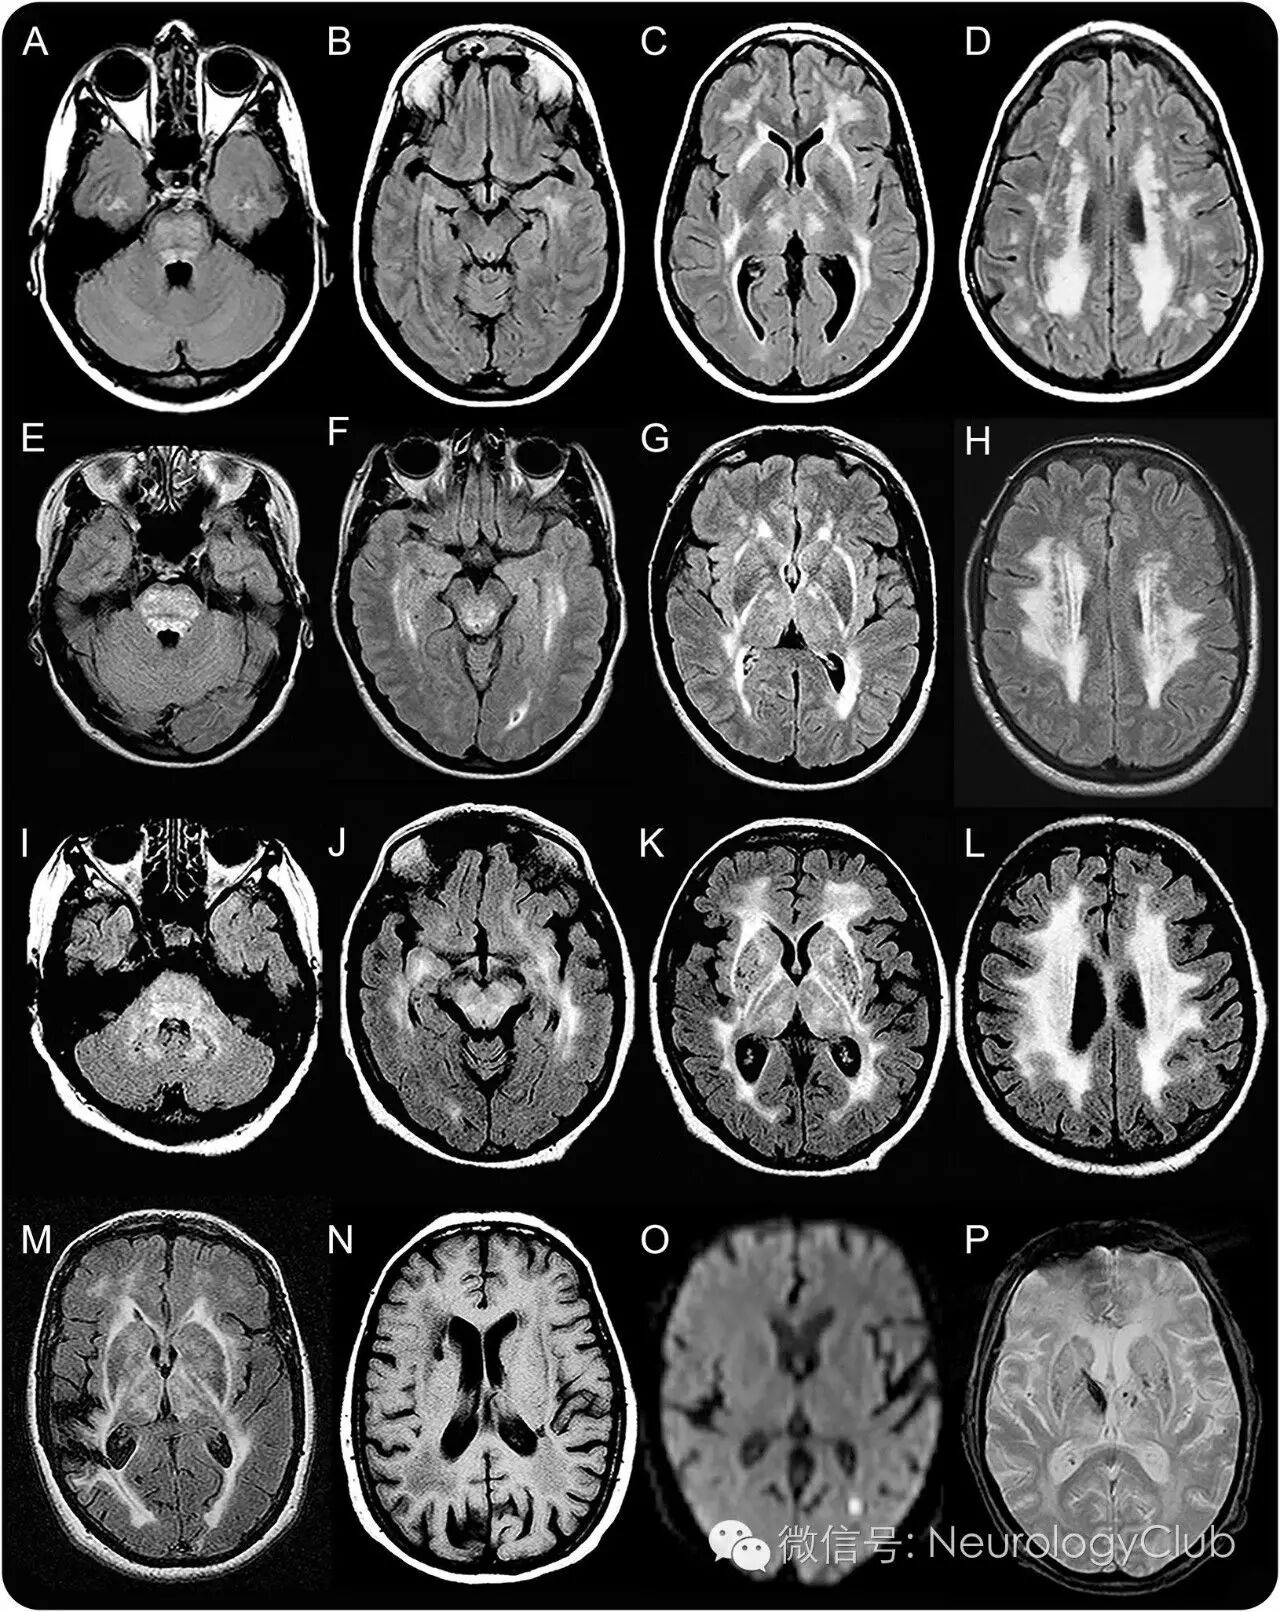

影像学表现

T2/FLARI序列上多表现为脑室旁和深部白质的信号改变,主要位于额顶叶,年轻患者病变呈局灶分布。多不累及颞叶白质和颞极。此外,基底节、丘脑、内囊、外囊和脑干(特别是脑桥和中脑红核)可见小的多灶性信号异常。年长者中病变多融合,分布更广泛。DWI上部分病灶可见弥散受限。另外,随着年纪的增长,脑梗死和脑微出血越显著。

图1:患者F2-2(39岁)(A-D),F1-IV6(46岁)(E-H),F1-III1(67岁)(I-L)和F1-III5(69岁)(M)的轴位MRI图像FLAIR序列;患者F1-III4(73岁)(N)的MRI图像T1序列;患者F1-IV8(53岁)(O)的MRI图像DWI序列;患者F1-III2(P)的MRI图像GRE序列。头颅MRI显示多灶或融合的白质异常,主要分布于额顶叶深部和脑室旁白质(B-D,F-H,J-L),基底节、丘脑、内囊和外囊(C,G,K)。即使年龄小,脑桥也可显示多灶的T2高信号病变(A和E)。白质病变在年长患者中更广泛(比较图A-H和I-L)。患者F1-III5有一个位于右侧额顶叶的大梗死灶(M)。脑室旁白质可见小的囊性梗死灶(N)。有些梗死灶尚处于急性期,DWI高信号(O)且ADC低信号(图未显示)。基底核和丘脑可见微出血和小的出血灶(P)